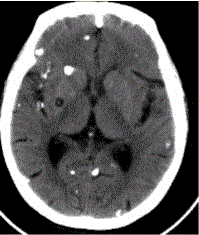

问题 患者男,45岁。头痛、癫痫10余年。查体:无发热,双侧肢体肌力正常。脑电图示双侧额颞叶棘波放电。CT表现如下图。 头颅CT检查中,描述不正确的是

选项 A.囊虫存活时(活囊虫),周围脑实质有显著水肿 B.囊虫存活时,周围脑实质没有水肿 C.囊虫死亡后(死囊虫),周围脑实质有显著水肿 D.囊虫死亡后,周围脑实质不再有水肿 E.无论囊虫存活与否,周围均有水肿 F.囊虫钙化沿血管分布 G.囊虫内可见头节

答案 ADEF